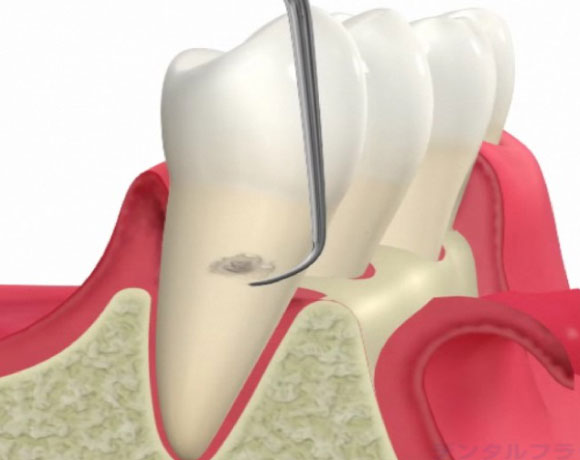

進行した歯周病は初期治療では治らない場合もあります。歯周ポケットが深いところは器具が届かないところがあるからです。溝が深くなればなるほど器具の到達率な低下し歯石は取り残しになります。

歯周病外科処置

歯周初期治療後改善しない場合、歯茎を切開して深いポケットの歯石を取ります。

歯肉弁剥離掻把術